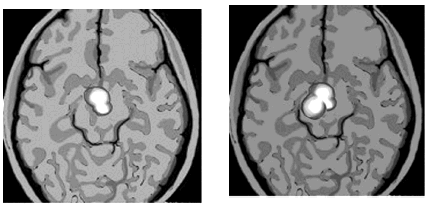

Ниже показаны результаты сканирования мозга «безумно влюбленного» человека и кокаинового наркомана. Убедитесь, что они почти идентичны.

На левом снимке показан участок мозга, активизирующийся у «безумно влюбленного» человека. На правом снимке показан участок мозга, который активизируется при употреблении кокаина